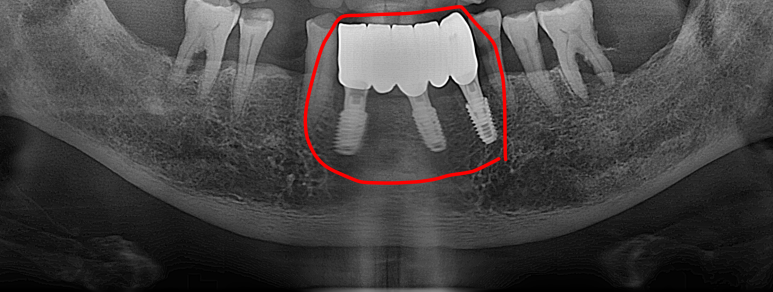

2026년 3월 5일에 촬영된 최종 방사선 사진입니다.

첫 내원일로부터 약 6개월간의 치료 과정이 안정적으로 마무리되었습니다.

하악 전치부에는 임플란트를 지지대로 삼아 브릿지 형태의 보철물이 체결되었고, 뼈가 부족했던 좌측 상악 어금니 부위 역시 상악동 거상술을 통해 튼튼하게 보철물이 완성되었습니다.